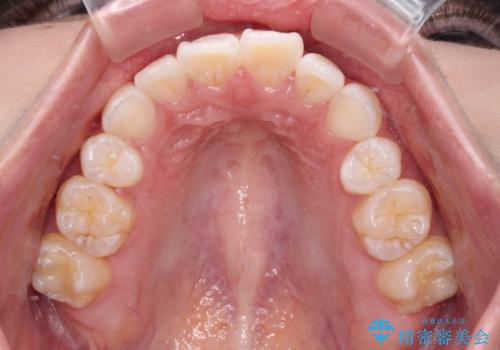

- 上下前歯の叢生を気にして来院された患者様です。

インビザラインでの治療を希望されていて、デコボコの程度が中等度であり、安価なパッケージにて対応可能と判断されたため、インビザライン・モデレートを用いて矯正治療を行うこととしました。

インビザライン・モデレートは、製作できるアライナーの枚数に制限があるため、移動可能な量に限りがあるものの、インビザライン・ライトよりも枚数が多いため、幅広い症例に対応可能です。